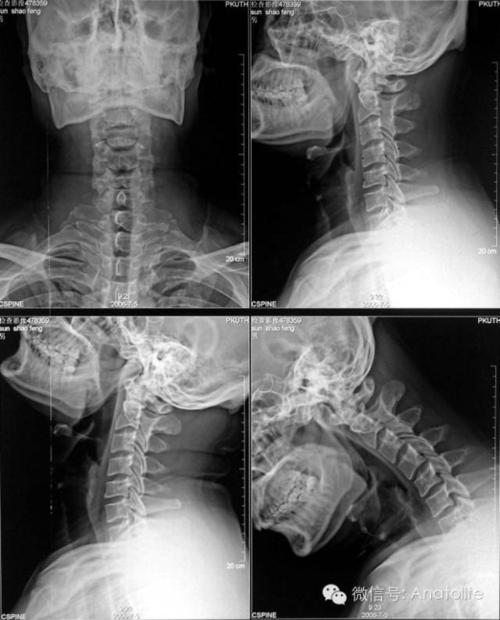

颈椎正侧位备孕可以拍片吗

根据现有的辐射原理,主要分为CT、x射线以及拍片。x射线电离辐射力强辐射量小,而x射线的电离辐射并不直接而确定。

颈椎拍片是怎么处理